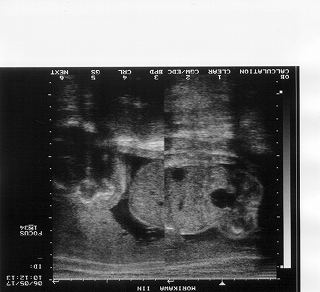

赤ちゃんは745gで今のところ女の子っぽいです(^_^)v

左側が頭部です。